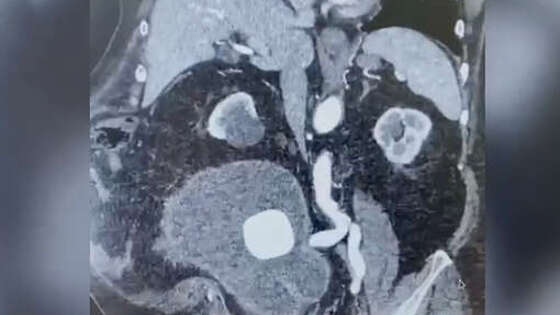

Медики Петербурга спасли пациента с большим количеством жидкости в мочевом пузыре, которую приняли за новообразование. Об этом сообщает Елизаветинская больница в официальном сообществе во "ВКонтакте". В медучреждение обратился 70-летний пенсионер, которого перевели из другой клиники с диагнозом: "Гигантское образование брюшной полости". Во время исследований выяснилось, что у мужчины перерастянут мочевой пузырь. Установив мочевой катетер, врач выпустил из пациента почти девять литров мочи. У пациента обнаружили хроническую задержку мочи, цистит и множественные камни мочевого пузыря. На данный момент пенсионер находится на амбулаторном лечении, но скоро его госпитализируют для планового осмотра. По словам медиков, этот случай является уникальным, так как нормальный объем мочевого пузыря у мужчины достигает 700 миллилитров. Самый большой объем органа зафиксировали у гражданина Индии. Из его организма вывели 11 литров мочи.